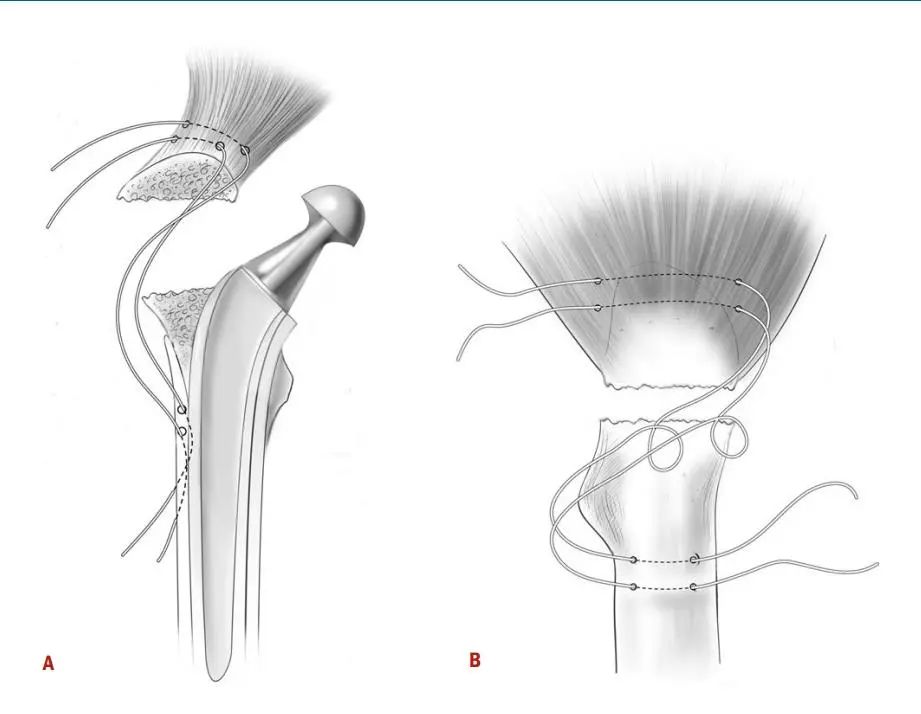

图2:说明大转子张力带钢丝固定技术图。A和B:髋关节正位和侧位,显示两根钢丝穿过股骨外侧皮质的钻孔,位于溶骨性病变下方远端,上方大粗隆尖端,呈八字形。C和D:髋关节正位和侧位,显示8字形钢丝在扭转前的位置,而助手使用复位钳将大转子的碎片重新接近股骨近端。E和F:髋关节正位和侧位,显示用颗粒状同种异体骨填充缺损处并用钢丝紧紧缠绕后,大转子重新附着。

图4:A和B图示大转子斜向环扎钢丝固定图。髋关节正位图(A)和侧位图(B)显示一根金属丝绕过大转子和小转子,用于固定大转子骨折并大转子和小转子骨溶解,然后用颗粒状同种异体骨移植充分填充溶骨病变。